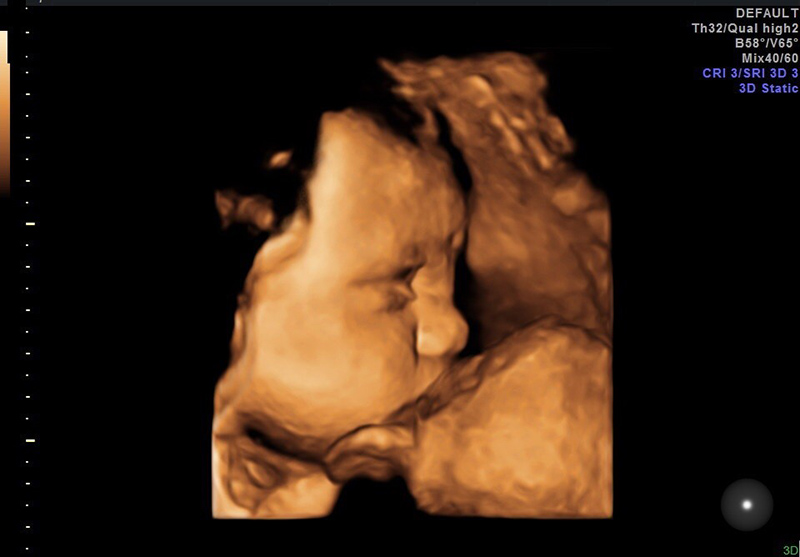

– Mẹ có thể nhìn thấy tóc, lông mày, lông mi và móng của bé đã mọc đầy đủ qua màn hình siêu âm.

– Não bộ đã phát triển hoàn thiện và lúc này bé bắt đầu có các biểu cảm như: nheo mắt, mỉm cười, thè lưỡi, chu miệng,… Hơn thế nữa, lúc này bé cũng đã có những hành động như tự di chuyển hay là nhắm mắt lại để tránh ánh sáng mạnh xuyên qua bụng mẹ.

Mẹ có thể nhìn thấy và cảm nhận được sự thay đổi của em bé so với những tháng trước. Lúc này, em bé đã hoàn thiện hết mọi đường nét về khuôn mặt và cơ thể. Chính vì vậy, lúc này mẹ bầu đã nhìn thấy được hình hài và cảm nhận được những hoạt động đáng yêu trong bụng mẹ của em bé.

- Siêu âm thai: Thường thì bác sĩ sẽ chỉ định siêu âm 4D cho các mẹ bầu vì nó có thể đưa ra hình ảnh rõ nhất của em bé.